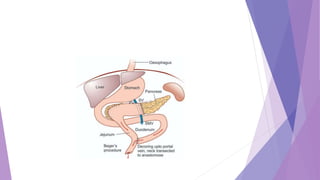

 Puestow’s operation—As the duct is dilated more than 8 mm, duct can easily

be opened longitudinally. After removing all stones from the duct, it is

anastomosed to the jejunum as side to side Roux-en-Y anastomosis. In

Puestow’s operation spleen is removed.

 The anterior surface of the pancreatic duct is opened

 After all stones are removed, a standard Roux-en-Y is used to create a two-

layer lateral pancreaticojejunostomy.

 The modified Puestow procedure provides palliation of pain in 80% of cases

 Puestow and Gillesby's longitudinal pancreaticojejunostomy